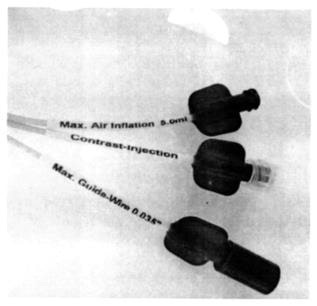

На фигуре 1:

фиг. 1

«порты» на «проксимальном конце литоэкстрактора» (соответственно, для введения: а) воздуха, б) контрастного вещества, в) металлического проводника).